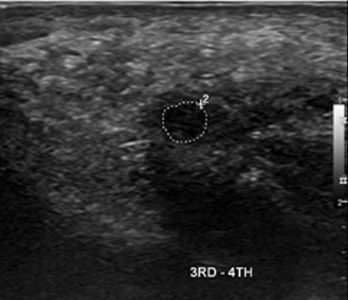

51세

여성 지간신경종

Before

2019.05.16

After

2020.02.08